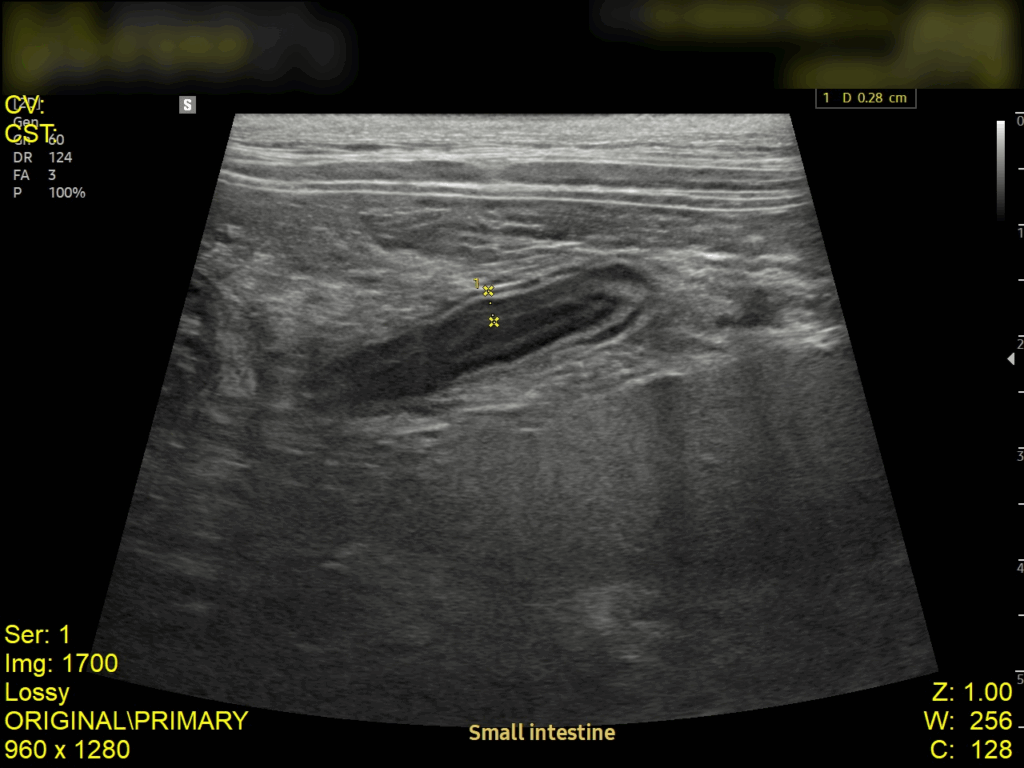

강아지 폐렴 치료 케이스 – 강서구 동물병원

강아지의 호흡이 갑자기 빨라지거나 얕고 가쁜 호흡을 반복한다면 단순 감기나 피로로 넘기기 쉽지만, 실제로는 폐렴(Pneumonia) 과 같은 중증 호흡기 질환일 가능성이 높습니다. 오늘은 산책 이후 갑작스럽게 호흡곤란이 발생한 13살 강아지의 사례를 통해, 폐렴의 진단 과정과 치료, 그리고 회복까지의 경과를 소개드리겠습니다. 강아지 폐렴 치료 케이스 이번 환자는 13살 믹스견의 중성화한 암컷 강아지로, 보호자님께서는 “3일 전 산책 […]